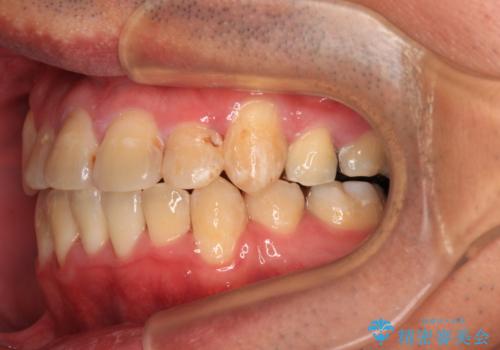

- 上下の八重歯やデコボコを気にして来院された患者様です。

上下ともに八重歯が顕著であったので、上下左右第一小臼歯4本を抜歯し、ワイヤー装置にて矯正治療を行うこととしました。

結婚式をきっかけに矯正治療を決意したとのことでしたが、挙式までの期間があまりにも短かったために、結婚式後に治療を開始することとなりました。

1年以上のゆとりを持って矯正治療を始める必要があります。